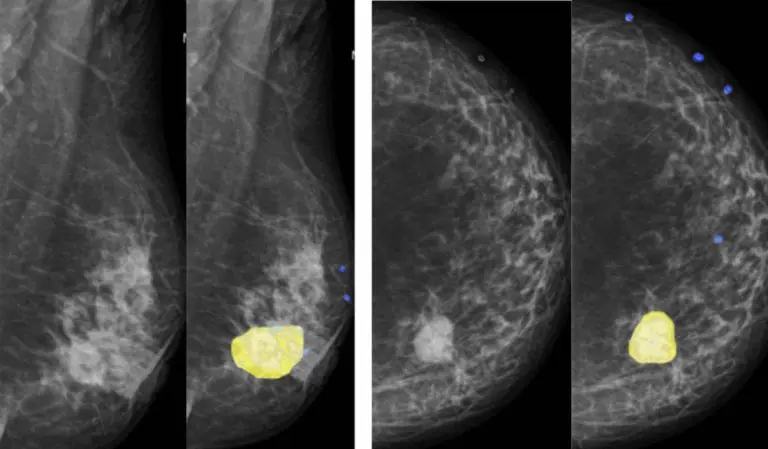

AI for Mammography

Breast cancer analysis involves inspecting mammograms to detect lesions and tumors.

With specialized resources for this exam modality, artificial intelligence can perform the automatic segmentation of breast masses, showing the constant evolution in mammography analyses and suggesting breast findings with density classification and lesion malignancy (BI-RADS). Resources like this can also help with screening, indicating priority of care.